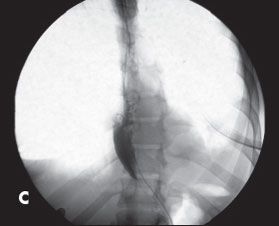

Esophagogastroduodenoscopy revealed a mildly dilated lower third of the esophagus (A). CT demonstrated a dilated esophagus (B). A barium swallow showed the classic “bird’s beak” appearance of the distal esophagus with proximal esophageal dilatation (C and D). A diagnosis of achalasia was made.